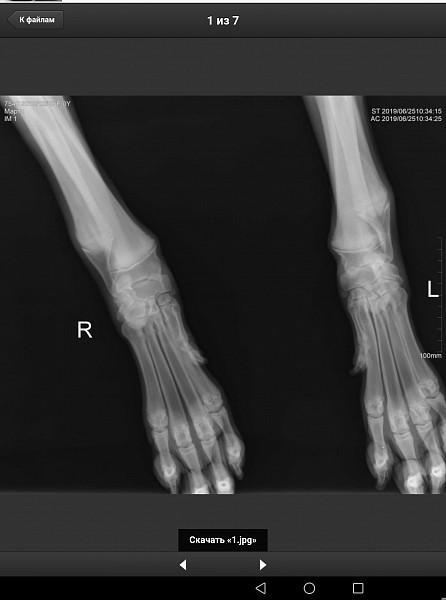

У нас немецкий дог, девочка, 6 месяцев, привита по возрасту. Поставлен диагноз Расслаивающий остеохондрит плечевого сустава (мышь плечевого сустава). Сказали, нужна операция по зачищению этого сустава. Как можно скорее.

Есть рентгеновский снимок. Прошу вас прокомментировать его, правильный ли диагноз? Как срочно нужно оперировать, если подтвердится диагноз? Какой период реабилитации? И, что нас ожидает в будущем, от чего могла развиться болезнь, наследственное это или нет, что делать, чтобы предупредить заболевание суставов других лап?

Здравствуйте. Судя по описываемым вами симптомам у собаки, действительно имеется поражения хрящевой поверхности какого-то сустава грудой конечности. На предоставленных вами снимках, затруднительно тщательно рассмотреть суставные поверхности. Ярко выраженной патологии хряща (расслаивающий остеохондрит не просматривается). Для подтверждения или исключения данной патологии наиболее оптимальным является компьютерная томография. При подтвтерждении диагноза, основным методом лечения является хирургическое вмешательство, направленное на устранение фрагментированного участка хряща и зачищении дефекта для формирования на месте поражения волокнистого хряща.